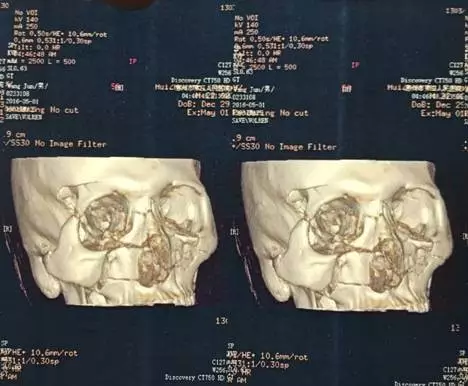

患者王某,因車禍致頭頜面部疼痛出血1小時入院,經(jīng)三維CT重建示:上頜骨lefortⅢ骨折,雙側顴骨復合體粉碎性骨折等。

上頜骨Lefort Ⅲ骨折